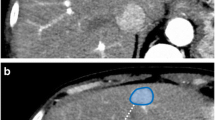

Radiology teaching file repositories contain a large amount of information about patient health and radiologist interpretation of medical findings. Although valuable for radiology education, the use of teaching file repositories has been hindered by the ability to perform advanced searches on these repositories given the unstructured format of the data and the sparseness of the different repositories. Our term coverage analysis of two major medical ontologies, Radiology Lexicon (RadLex) and Unified Medical Language System (UMLS) Systematized Nomenclature of Medicine Clinical Terms (SNOMED CT), and two teaching file repositories, Medical Imaging Resource Community (MIRC) and MyPacs, showed that both ontologies combined cover 56.3% of terms in the MIRC and only 17.9% of terms in MyPacs. Furthermore, the overlap between the two ontologies (i.e., terms included by both the RadLex and UMLS SNOMED CT) was a mere 5.6% for the MIRC and 2% for the RadLex. Clustering the content of the teaching file repositories showed that they focus on different diagnostic areas within radiology. The MIRC teaching file covers mostly pediatric cases; a few cases are female patients with heart-, chest-, and bone-related diseases. The MyPacs contains a range of different diseases with no focus on a particular disease category, gender, or age group. MyPacs also provides a wide variety of cases related to the neck, face, heart, chest, and breast. These findings provide valuable insights on what new cases should be added or how existent cases may be integrated to provide more comprehensive data repositories. Similarly, the low-term coverage by the ontologies shows the need to expand ontologies with new terminology such as new terms learned from these teaching file repositories and validated by experts. While our methodology to organize and index data using clustering approaches and medical ontologies is applied to teaching file repositories, it can be applied to any other medical clinical data.